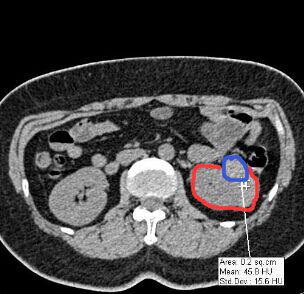

某醫院的外科醫生需要做一個3D腎臟模型,但CT片拍出的二維圖像中,其腫瘤位置只是通過灰色的色階來表示(臨床應用中稱之為CT值),如上圖中紅色圈出來的是腎臟截面,藍色則為腫瘤位置。從圖中可以看出,在CT片子中藍色部分僅僅比紅色部分要白一點。